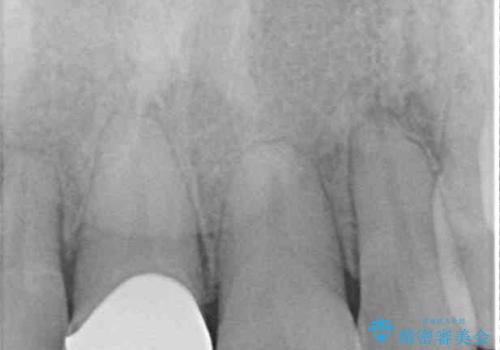

- ぶつけて前歯が折れてしまったとのことで来院された患者様です。

折れてしまった前歯は軽傷であり、歯内の歯髄に影響は及んでいませんでした。

通常では速やかにオールセラミッククラウンにて補綴治療を行うのですが、デコボコしている歯列も気になっていたため、事前に矯正治療を行うこととしました。

上顎歯列の叢生が著しかったため、上顎左右第一小臼歯2本を抜歯し、目立たないワイヤー装置にて治療を進めることとしました。